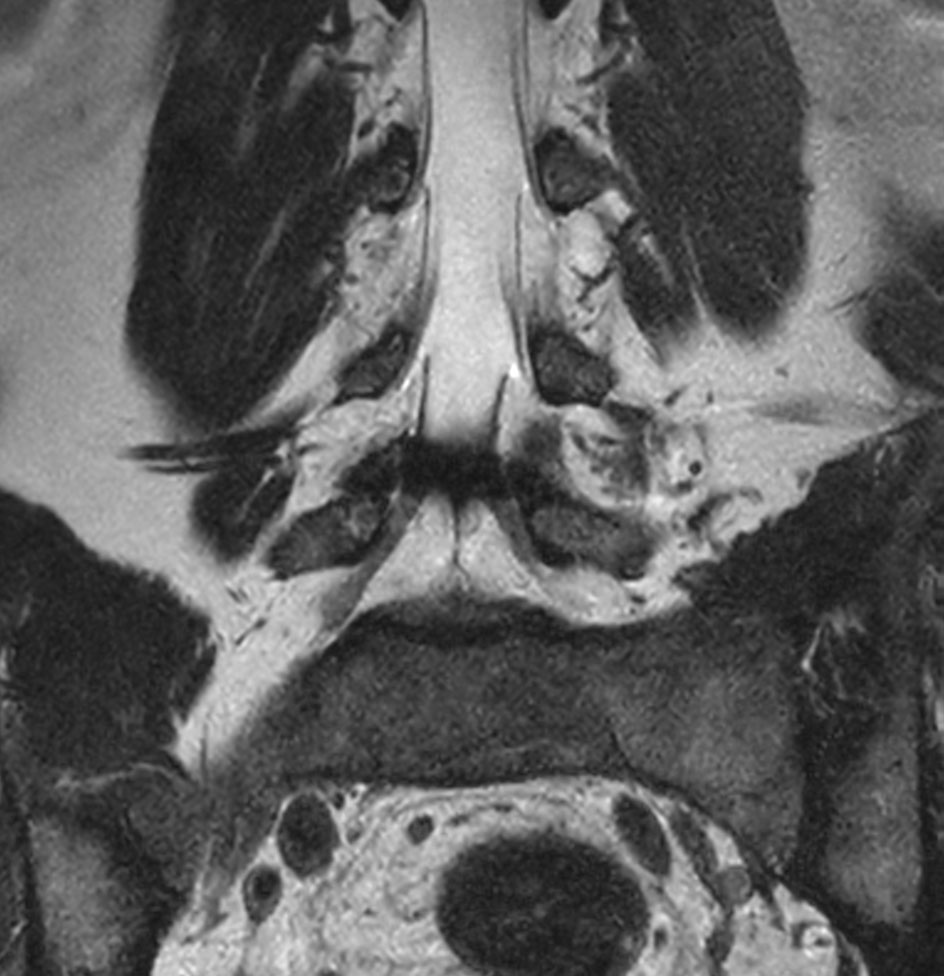

Patient with a lumbar spine bulging disc.

Coronal T2w mDIXON XD TSE (In-Phase)